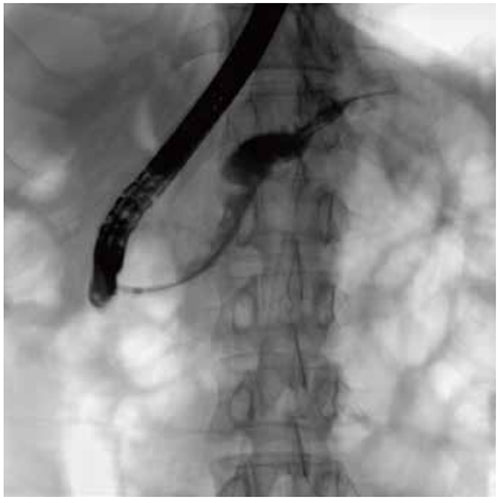

The FPD can be lifted in a wide range to flexibly adjust SID and be close to the examination area for clearer fluoroscopic images.

When fluoroscopy is started, the high-pressure injector automatically injects the contrast agent, which simplifies the doctor’s workflow and obtains high-quality angiography

images in a short time.